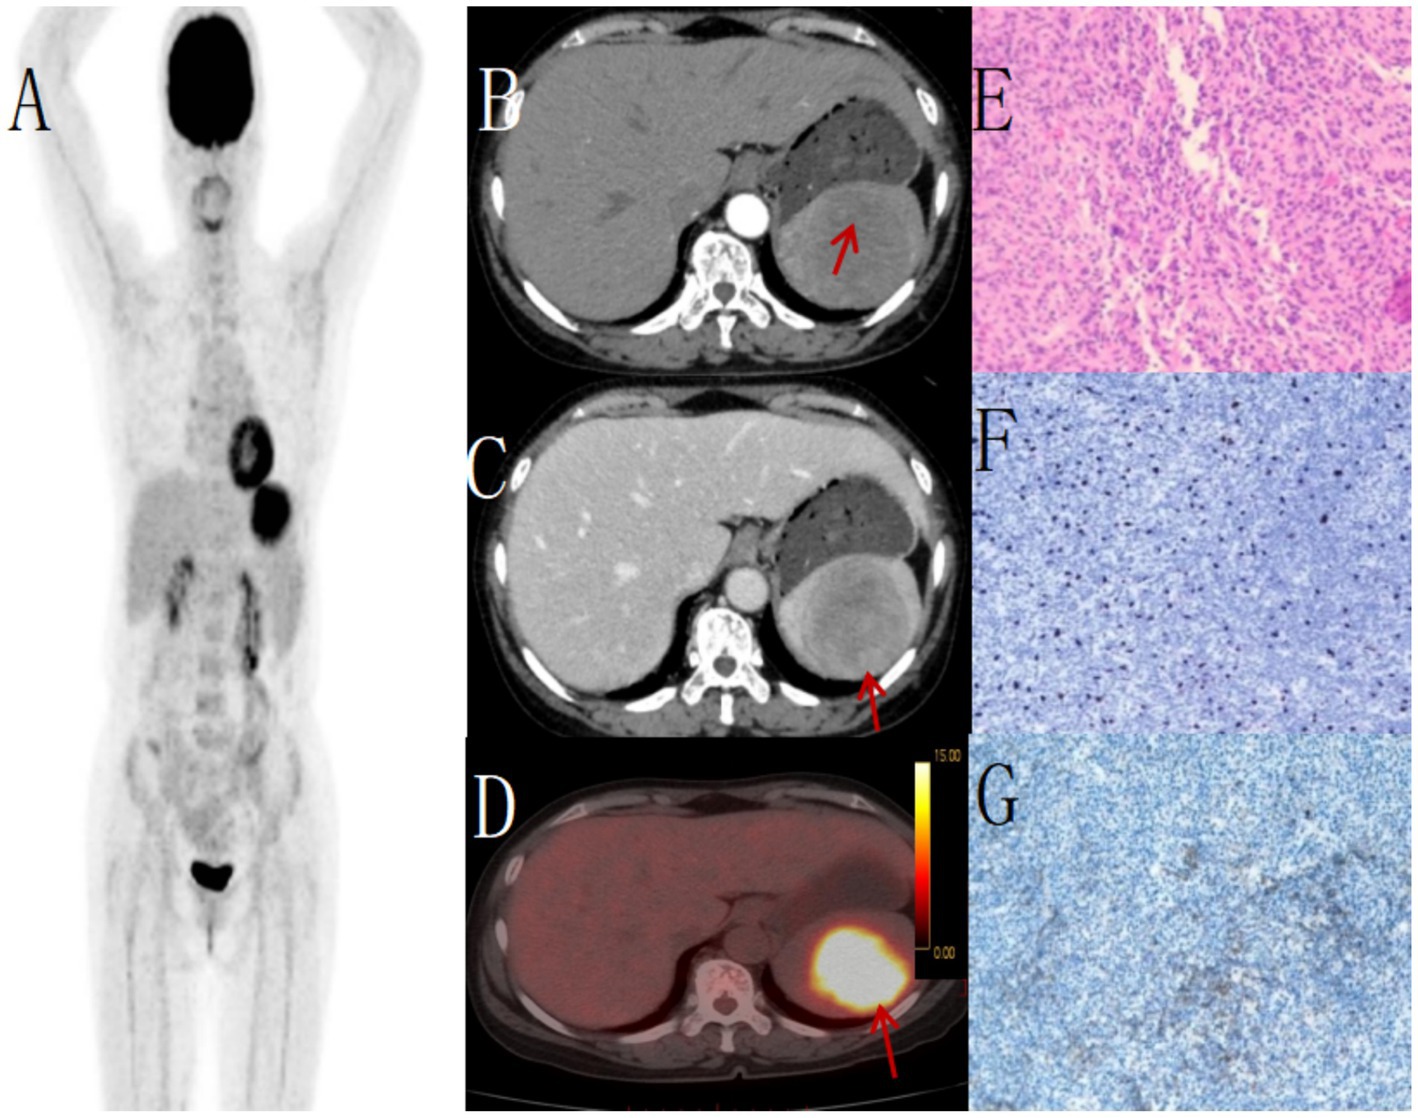

Figure 1

Female, 85 years old, diffuse large B-cell lymphoma. (A) whole body MIP, (B) axial fusion, (C) coronal fusion, (D) sagittal fusion, (E) axial CT, (F) coronal CT, (G) H-E × 200. 18F-FDG PET/CT demonstrated splenomegaly with an irregular soft tissue density mass (maximum cross-sectional dimension 17.7 × 8.5 cm) showing heterogeneous density and small hypodense necrotic areas. The lesion exhibited uniformly increased radiotracer uptake with a maximum standardized uptake value (SUVmax) of 14.4 (arrow, B–D). CT demonstrates an enlarged spleen with heterogeneous attenuation, showing multiple nodular and small patchy hypodense lesions. On contrast-enhanced scans, the spleen exhibits mild enhancement, while the necrotic areas show no significant enhancement (E). PET/CT-guided splenic biopsy confirmed the diagnosis of diffuse large B-cell lymphoma, non-germinal center subtype (G).